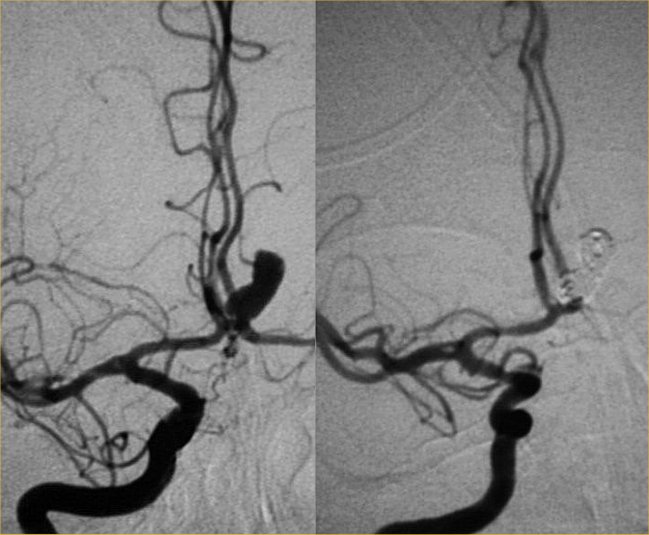

Stentassisted coil embolization of MCA aneurysm via a transposterior

From jnis.bmj.com

Comparison of techniques for stent assisted coil embolization of Embolization Coil Procedure for certain people with brain aneurysms, this minimally invasive alternative procedure to open surgery produces better outcomes. In the elective settings, coils can be used for the treatment. embolization is a minimally invasive procedure to treat an aneurysm by filling it with material that closes off the sac and. what is endovascular coiling? endovascular coiling is. Embolization Coil Procedure.